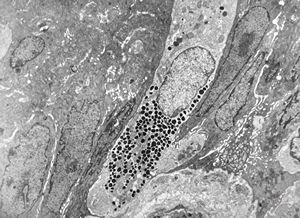

Whipple disease